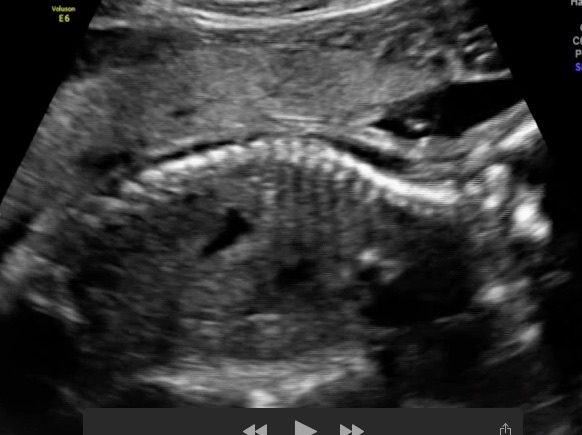

Attachment 22643was able to get another pic..hope this is help..so lets guess this one..